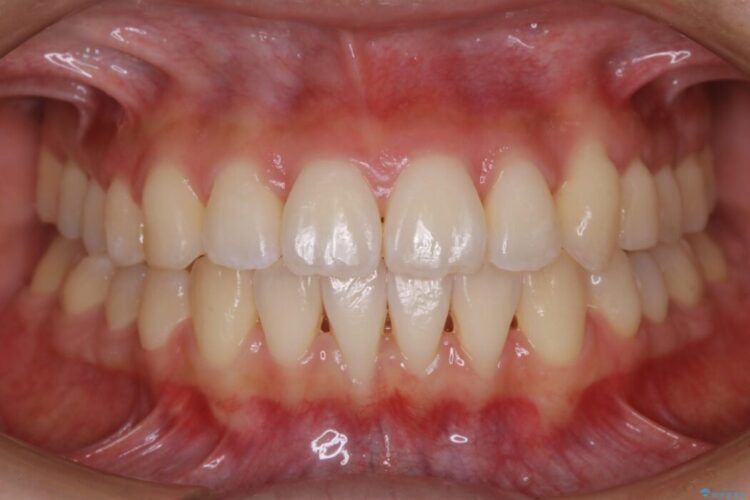

治療後について

治療前と治療後を見比べると口元の見た目の変化が良く分かります。

本症例では奥歯から順に移動させるため前歯の変化を感じるには時間が掛かりましたが、インビザライン装置とマイクロインプラントを併用することで健康な歯を抜歯することなく歯列をきれいに整えることができました。